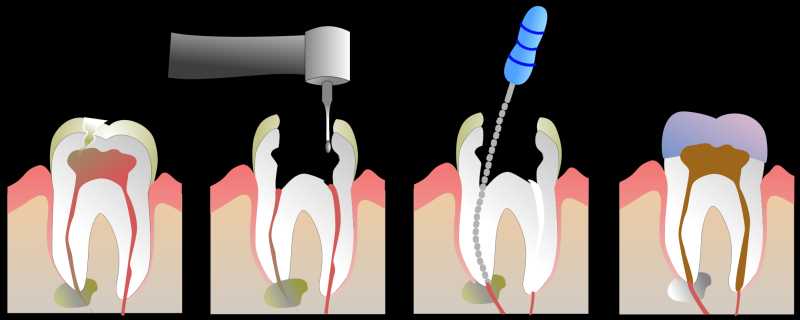

Inicio Especialidades Endodontia